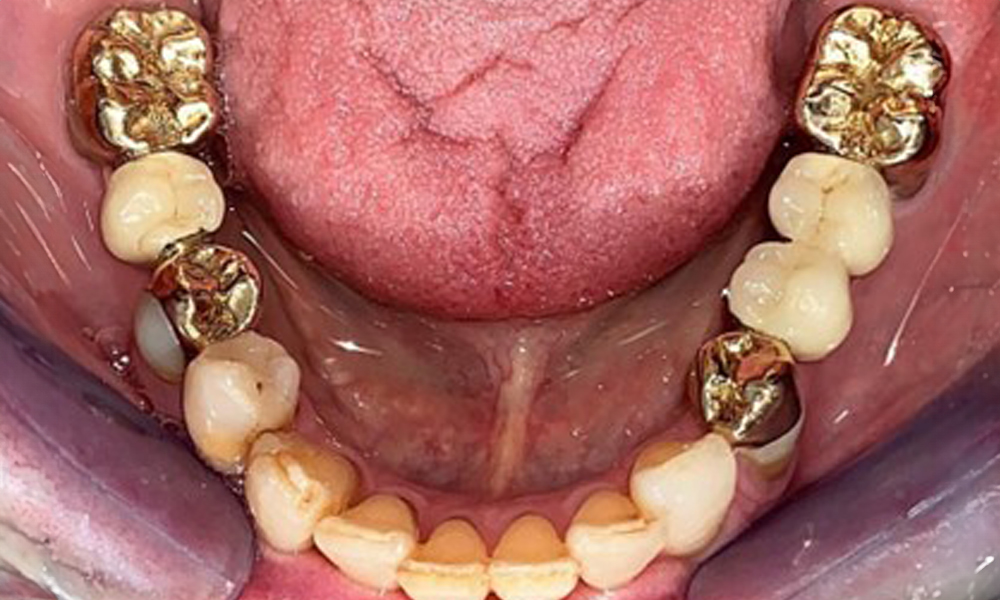

На пациентката е поставена комбинирана подвижна горночелюстна телескопична протеза преди повече от 25 години (фиг. 1, фиг. 2, фиг. 3) и тя е много доволна от протезите си. Пациентката има адекватна фиксирана протеза за долната челюст (фиг. 4).

Денталните открития са следните: Комбинирани снемаеми протези на импланти и телескопични протези, поддържани от зъби, на импланти 15, 13, 21, 23, 24, 25 и зъб 11 (фиг. 1, фиг. 2, фиг. 3). Пациентът е снабден с фиксирана долночелюстна протеза. Над зъби 37-34 и 45-47 бяха налични адекватни мостове (фиг. 4), краищата на коронките бяха интактни и нямаше активен кариес. Върху зъб 43 имаше композитна пломба с маргинална празнина. Имаше рецесия на долната гингива, която разкриваше от 1 до 3 mm от кореновата повърхност. Това се отнася и за 11.